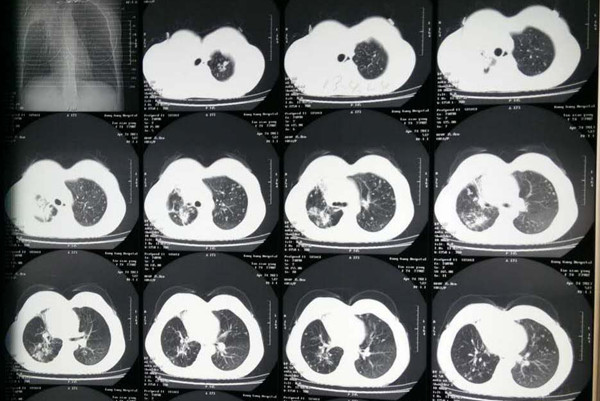

然后患者严格按照该治疗方案进行治疗调养。经过一段时间治疗以后,结核性胸膜炎病人胸腔积液很快吸收,结核病症状也很快消失,同时出现复发的概率也是非常低。